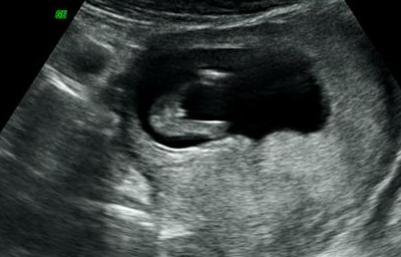

Hi! We had our 3D scan yesterday at 12w1d. Tech says its a girl, any thoughts?

I'm sorry but maybe to early for a potty...

Too early for a potty shot.

Agree with above, too early for potty shot. Boys and girls parts look the same at this gestational age, you need the nub shot.